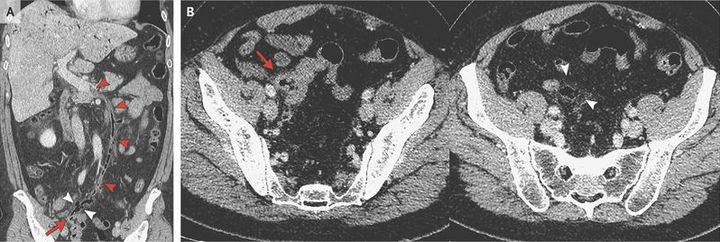

A 45-year-old man presented to the emergency department with a 4-day history of fever and jaundice. Initial workup revealed leukocytosis and elevated aminotransferase levels that indicated possible cholangitis. Despite broad-spectrum antibiotic therapy, the patient did not have clinical improvement. A computed tomographic scan showed acute perforated sigmoid diverticulitis (Panels A and B, arrow) and gas in the mesentery (Panels A and B, white arrowheads). In addition, there was gas in the inferior mesenteric vein extending to the splenic vein up to the origin of the portal vein (Panel A, red arrowheads), a finding that was consistent with pylephlebitis. Fat stranding around the inferior mesenteric vein, indicating inflammation, was also noted, and there were peripheral linear collections of gas in the liver. An emergency Hartmann’s procedure was performed, and the patient received antibiotic therapy against Escherichia coli, which grew on culture, with no anticoagulation therapy. He had clinical improvement and was discharged 18 days after surgery. Pylephlebitis is an infective suppurative thrombosis of the portal vein, its branches, or both and is typically associated with intraabdominal infections, such as diverticulitis, appendicitis, necrotizing pancreatitis, and inflammatory bowel diseases. Bacteroides fragilis and E. coli are the most common pathogens.